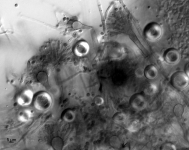

| Substrate: | left occipital brain biopsy, female 21 yr, who had a small bowel transplant 10 yr prior; histopathology + for Aspergillus-like hyphae | Location: | USA Nebraska, Omaha, University of Nebraska Medical Center (GEO: 41.255,-95.976) |

| Characters: | CULTURE CONDITIONS heavy ascomata on PDA - // HUMAN/ ANIMAL PATHOGEN cerebral aspergillosis in a small bowel transplant patient - // MOLECULAR SYSTEMATICS calmodulin sequence has 99% identity to 5 strains of E. echinulata in the GenBank - fide P. Iwen (Click for publications citing UAMH 10948) |